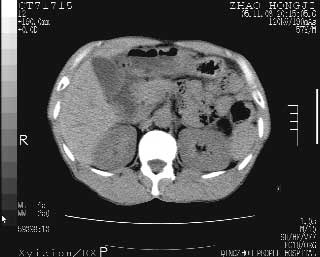

临床资料:男性,57岁,上腹部疼痛并5天,突然加重并延及全腹伴恶心5小时入院。胰淀粉酶化验在正常范围。检查:腹肌紧张,全腹压痛、反跳痛,尤以右上腹部为著。肠鸣音减低。血常规:wbc14.6x10/9, n:11.3x10/9 ,血压:135/90mmhg. 胸部透视:腹部肠腔轻度张气,未见其它异常改变。

肝右前缘少量积气,其他未见明显异常.考虑上消化道穿孔.

小网膜囊积气液,胃壁僵硬。考虑胃穿孔。

小膜网膜积液,肝缘气腹征,上消化道穿孔。

肝缘见少许气体,胰尾部见少许气体包饶(蓝色圈),12指肠上部或球部邻近胆囊周边也可见少许气体影(黄色圈),并忖托出胆囊壁,12指肠远段肠道内未见明显气体(白色箭)。

肝脏前缘见少量积气、胰尾部见少许气体包饶,肾前筋膜未见增厚,临床淀粉酶不高,意见:上消化道穿孔。

入院3小时后行剖腹探查术,见腹腔内大量脓性混浊液约1000ml,十二指肠球部溃疡穿孔,溃疡面约2.5x2cm,穿孔直径约0.6cm。胃内容物外益,周围组织炎性水肿明显。行十二指肠穿孔修补术。术后诊断:

1、十二指肠溃疡穿孔

2、弥漫性腹膜炎

对于少量的腹腔游离气体,ct检查较普通透视有绝对的优势,它不仅可以看到肝脏前上缘的气体,而且还能够看到小网膜区的游离气体。从而可以肯定诊断。各位分析战友的很好,感谢大家的参入!